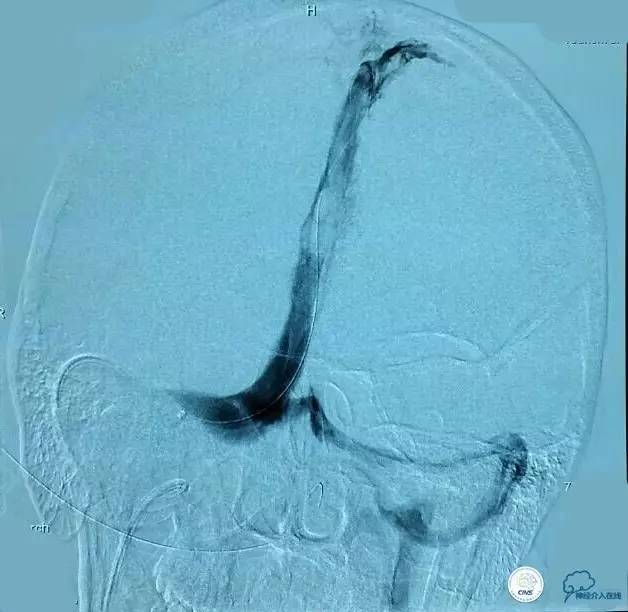

▼正位造影:

▼正位: